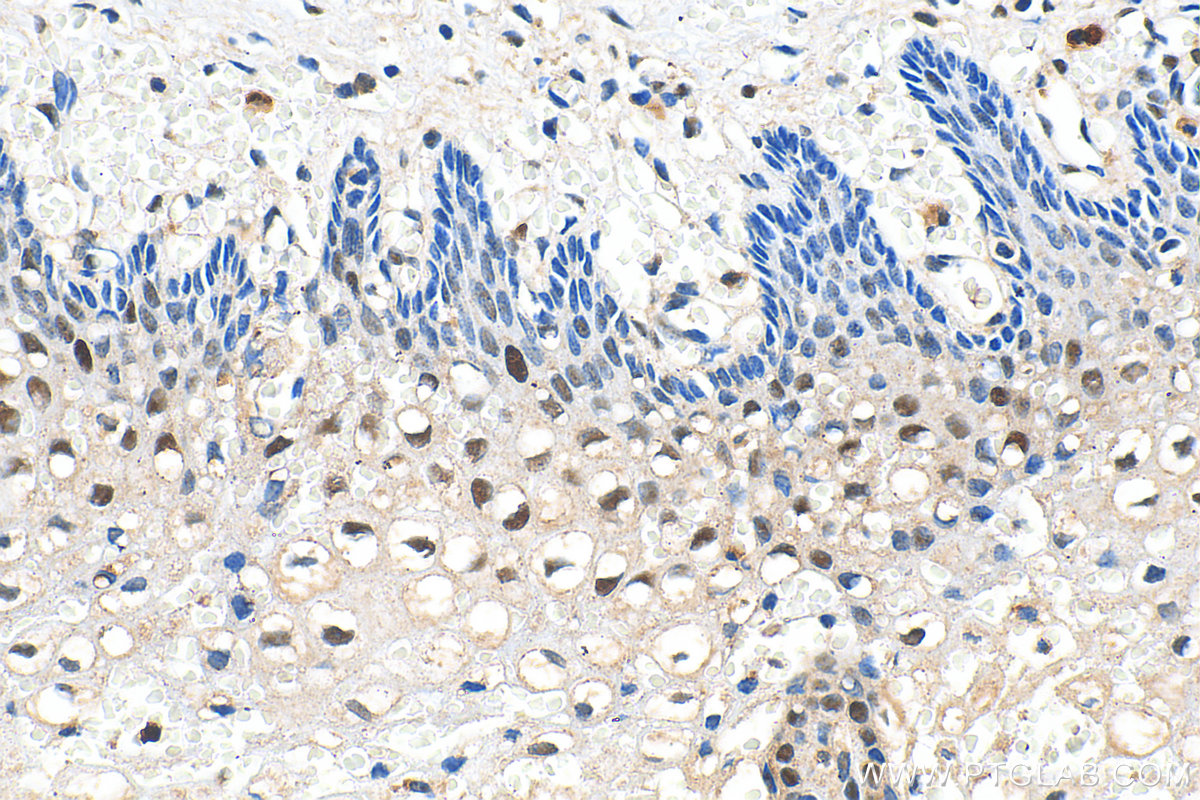

| Positive IHC detected in | human colon cancer tissue, human breast cancer tissue, human cervical cancer tissue, human kidney tissue, human stomach cancer tissue, human thyroid cancer tissue Note: suggested antigen retrieval with TE buffer pH 9.0; (*) Alternatively, antigen retrieval may be performed with citrate buffer pH 6.0 |

| Immunohistochemistry (IHC) | IHC : 1:5000-1:20000 |